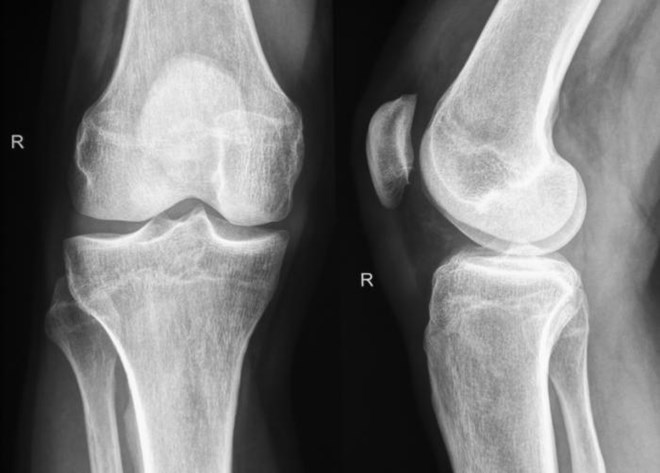

Nhóm nghiên cứu tại NU đã bắt đầu triển khai các thí nghiệm tập trung vào tái tạo xương hoặc sụn, trong đó các "ma trận" này bao quanh những tế bào sẵn có hoặc kết chặt xung quanh các nhân tố phát triển (gồm các protein chức năng thường được đưa tới các bộ phận trong cơ thể để hỗ trợ quá trình tái tạo khi có tổn thương).

Thí nghiệm cho thấy công nghệ "ma trận" đã giúp giải quyết vấn đề tái tạo mà không cần "động chạm dao kéo." Thông thường, để tiến hành phẫu thuật nối xương sống như là ghép mô xương các bác sỹ phải thực hiện theo các bước bắt đầu bằng việc lấy một phần xương từ một bộ phận khác của cơ thể bệnh nhân (thường là từ phần hông), sau đó đưa vào để nối các đốt sống.

Nhưng với kỹ thuật mới, không cần phải lấy phần xương ở chỗ khác đưa vào, nên không cần huy động quá nhiều các nhân tố phát triển, giảm một nửa chi phí, mức độ đau đớn cũng giảm đi trong khi nguy cơ thất bại cũng thấp hơn.